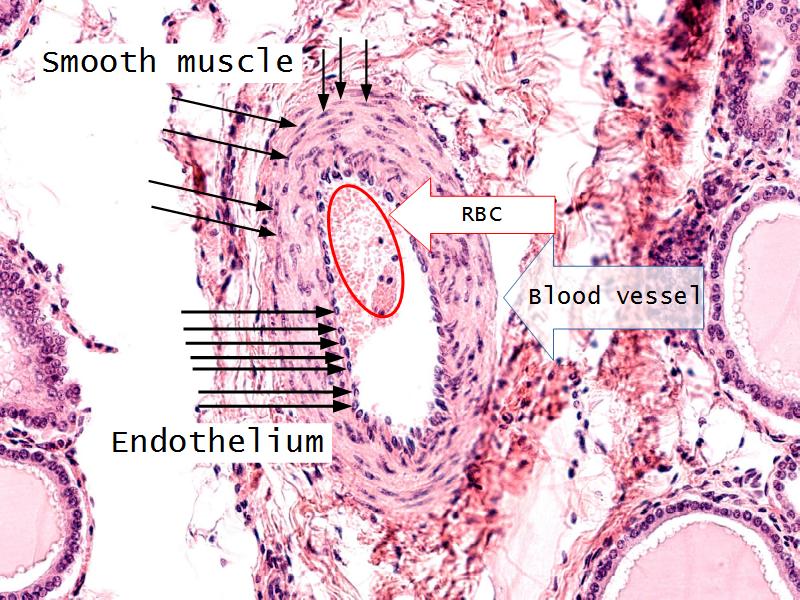

- Slide 52: Pituitary gland

- Slide 55: Thyroid gland

Pituitary gland

How does the pituitary and hypothalamus communicate?2 ways